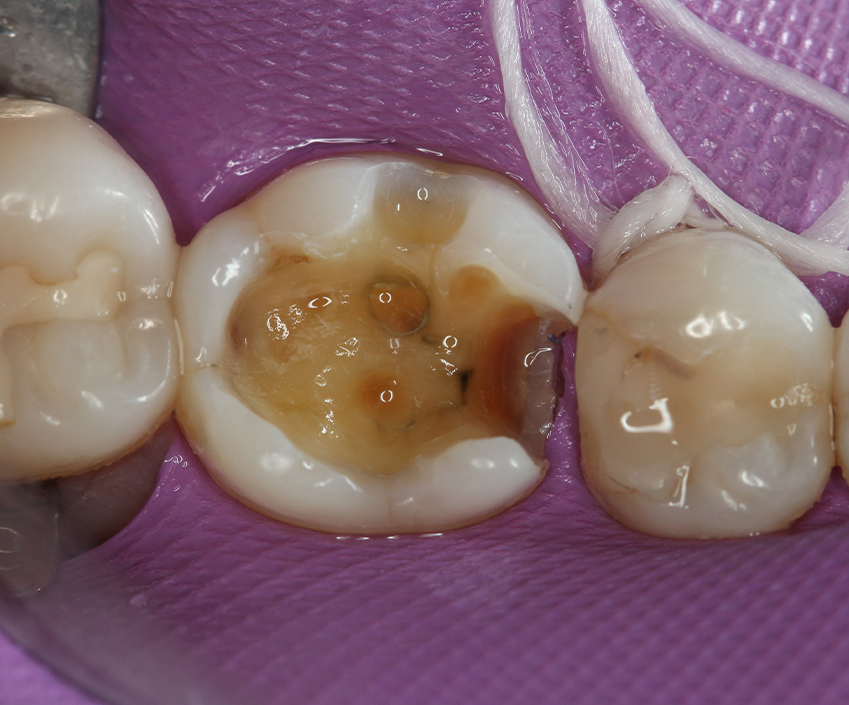

Selective enamel etching (30s) was performed, washed and completely air-dried with an oil-free air stream (Fig. 5). A universal adhesive (Adhese Universal, Ivoclar Vivadent) was applied (Fig. 6) by brushing it in the cavity, and excess of solvent was evaporated with oil-free air. The adhesive was light-cured (Bluephase 20i, Ivoclar Vivadent).

Fig. 5 Fig. 6